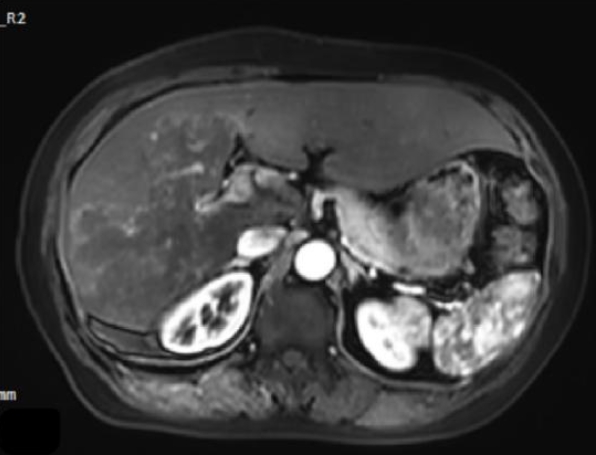

A fatal case of complex hepatic alveolar echinococcosis

Parasites, Hosts and Diseases 2026;64(1):98-103.